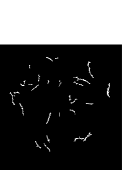

Figure 5: Vessel skeleton extraction. (a) The green channel of the fundus image Igsubscript𝐼𝑔I_{g}. (b) The vessel enhanced image Iiuwsubscript𝐼𝑖𝑢𝑤I_{iuw}. (c) The binary image T𝑇T. (d) The background regions T1subscript𝑇1T_{1}. (e) The candidate regions T2subscript𝑇2T_{2}. (f) The vessel regions T3subscript𝑇3T_{3}. (g) T4subscript𝑇4T_{4}: The preserved regions in T2subscript𝑇2T_{2}. (h) The combined regions of T3subscript𝑇3T_{3} and T4subscript𝑇4T_{4}. (i) The vessel skeletons S𝑆S.

III-A2 Vessel Skeleton Extraction

Vessel Skeleton Extraction aims to further distinguish the unknown regions and provide more information on blood vessels. In Section V(B)-”Vessel Segmentation Performance”, the effectiveness of vessel skeleton extraction will be presented. Firstly, a binary image T𝑇T is obtained by global thresholding the enhanced vessel image Iiuwsubscript𝐼𝑖𝑢𝑤I_{iuw}.

where t=Otsu(Iiuw)ε𝑡𝑂𝑡𝑠𝑢subscript𝐼𝑖𝑢𝑤𝜀t=Otsu(I_{iuw})-\varepsilon, ε𝜀\varepsilon is set as 0.030.030.03. Then T𝑇T is divided into three regions according to the Area𝐴𝑟𝑒𝑎Area feature:

T={T1if 0<Area<a1T2if a1Areaa2T3if a2<Area𝑇casessubscript𝑇1if 0<Area<a1subscript𝑇2if a1Areaa2subscript𝑇3if a2<AreaT=\left\{\begin{array}[]{rl}T_{1}&\text{if $0<Area<a_{1}$}\\ T_{2}&\text{if $a_{1}\leq Area\leq a_{2}$}\\ T_{3}&\text{if $a_{2}<Area$}\end{array}\right. (9)

In vessel skeleton extraction, the regions in T3subscript𝑇3T_{3} are preserved while the regions in T1subscript𝑇1T_{1} are abandoned. Then the regions in T2subscript𝑇2T_{2} with Extent>e2𝐸𝑥𝑡𝑒𝑛𝑡subscript𝑒2Extent>e_{2} && VRatior𝑉𝑅𝑎𝑡𝑖𝑜𝑟VRatio\leq r are preserved as T4subscript𝑇4T_{4}. Finally skeleton extraction [35] is performed on the combined regions of T3subscript𝑇3T_{3} and T4subscript𝑇4T_{4} in order to obtain the skeleton of blood vessels S𝑆S. An example of vessel skeleton extraction is shown in Fig.5.

After performing image segmentation and vessel skeleton extraction, the trimap of the input fundus image is generated (as shown in Fig.7(b)), which is composed of the background regions (B𝐵B), unknown regions (U𝑈U) and vessel (or foreground) regions (V=V2S𝑉subscript𝑉2𝑆V=V_{2}\cup S).